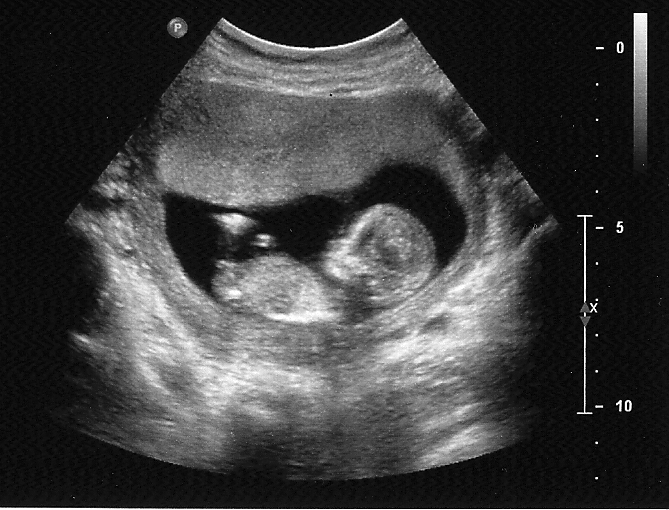

Just had my 12 week NT scan today! I am sooo bad with the guessing thing, but thought I would join in the fun of obsessing. I feel like a crazy person making myself wait "for real" until delivery!

Attachment 1908